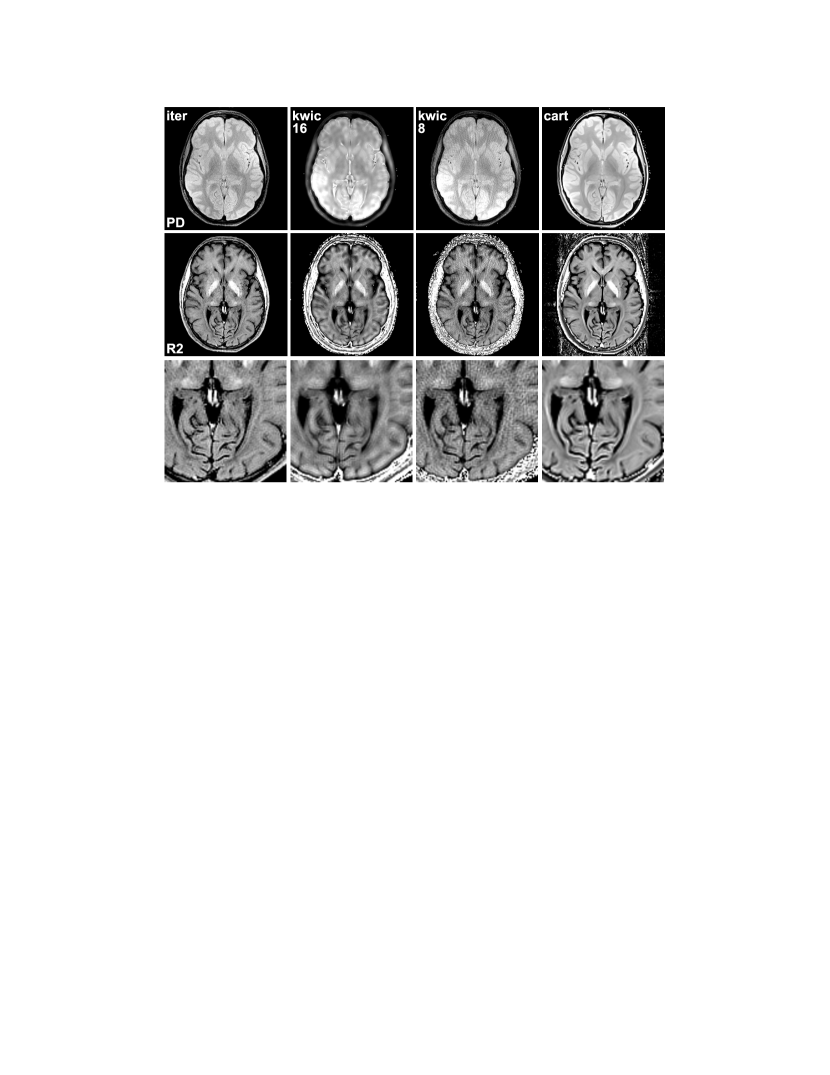

Figure 2: Spin-density maps (top) and relaxivity maps (bottom) estimated for a transverse section of the human brain in vivo (base resolution 224 pixels, FOV 208 mm, bandwidth 360 Hz/pixel) using the proposed method (iter), KWIC combining all 16 echoes (kwic 16), and KWIC combining only 8 neighboring echoes (kwic 8). Other parameters as in Fig. 1. For comparison, maps from a fully-sampled Cartesian reference data set are shown in the right column (cart). The bottom row shows magnifications of the relaxivity maps.

Figure 2 shows corresponding reconstructions for a transverse section of the human brain in vivo. Again, the KWIC reconstruction using 8 echoes suffers from streaking artifacts, while the maps involving all echoes appear fuzzy and blurry. In the latter case, the spin-density map is further contaminated by sharp hyperintense structures. This results from padding the high frequencies with data from late echoes which introduces components with T2 weighting and poses a general problem when sharing data with varying contrast. The iteratively calculated maps present without these artifacts. For comparison, maps from a fully-sampled Cartesian data set are presented, which show good agreement with the maps obtained from the iterative approach. Noteworthy, because the slice thickness was higher in the Cartesian acquisition, these maps show a slightly larger part of the frontal ventricles, which, however, is not related to the reconstruction technique.